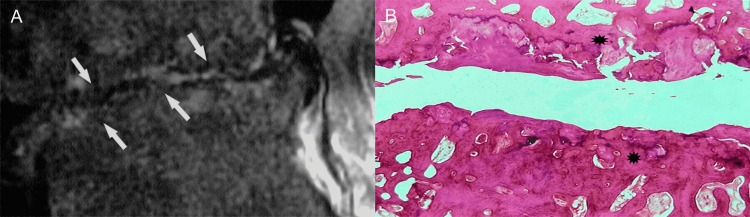

Besides traumatic disruption of the vertebral end-plate, the differential diagnosis of hyperintensity on T2-weighted images of the disc and the adjacent vertebral bodies includes infection (e.g., spondylodiscitis), inflammatory diseases (e.g., rheumatoid arthritis), and neoplasm (primary tumor or metastasis) (Figures 16A, 16B) [23-30].

Figure 16. Tumorous invasion of the vertebral end-plate and disc.

(A) Sagittal T2-weighted MR image shows metastatic breast tumor (asterisk) at the posterior portion of the S1 vertebral body infiltrating the vertebral endplate (arrow).

(B) Histologic section reveals mixed pattern of osteolysis and osteosclerosis in trabecular bone (asterisk) at the site of tumorous deposit. Note newly formed blood vessels (arrowheads) in the infiltrated disc. PLL, posterior longitudinal ligament.